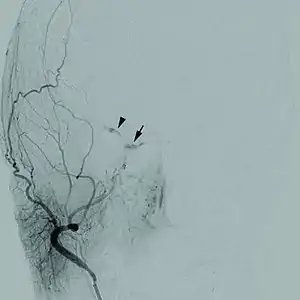

| Cerebral angiogram of a carotid-cavernous fistula | |